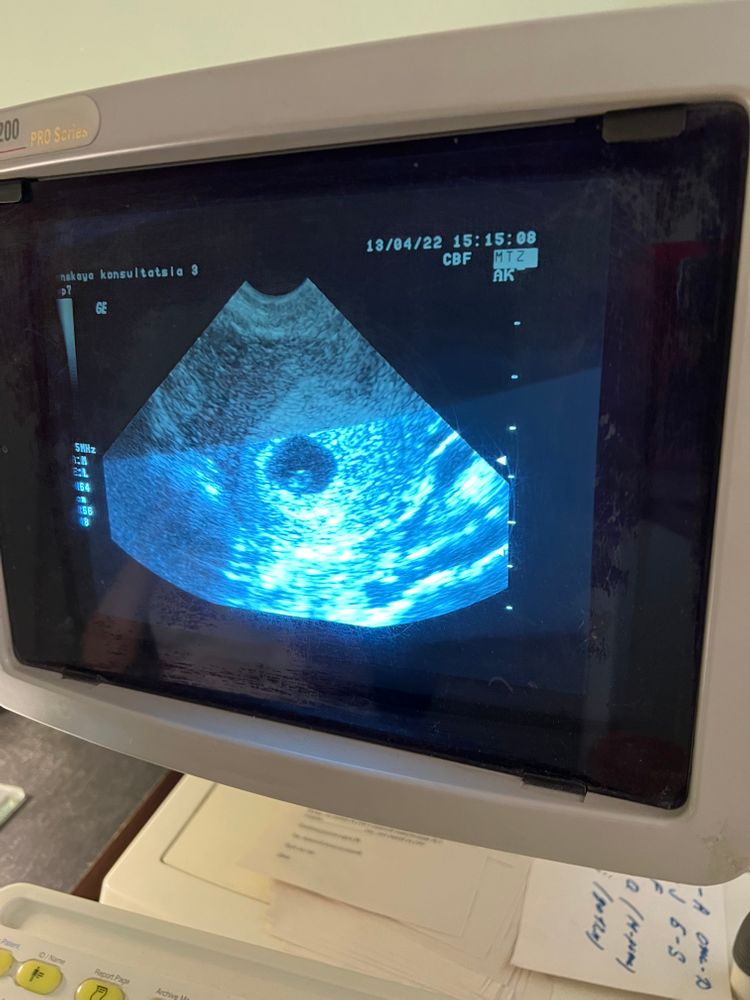

Девочки, вчера задавала вопрос про ЖК. В итоге обратилась не в ту, куда хотела и геморрой с записью, а в другую, где приняли без записи и сделали узи😂 Это, конечно, было сверхбыстро, но я уже решила для себя, что чем меньше знаю, крепче сплю: все в матке, сердечко стучит, размеры никакие не знаю, сфоткать экран дали. Выдали направления на анализы, завтра поеду сдавать мочу и кровь к 8 утра, а 27.04 мне уже на явку со всеми документами - поставят на учёт и возьмут мазок на флору🌷 Врач понравилась: молодая, современная. Дюф велела убавить с 4 таблеток до 3х до следующего приёма: аллилуйя, теперь ночью не надо вставать по будильнику! Теперь официально ставлю кружочек🥳